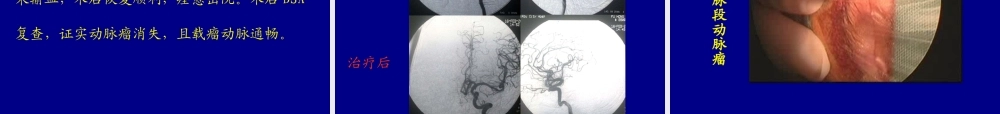

中南大学湘雅医学院附属海口医院海口市人民医院神经外科曹作为史克珊金虎李钢陈伟明陈焕雄陈晓东林鹏内镜辅助锁孔入路夹闭颅内动脉瘤中南大学湘雅医学院附属海口医院海口市人民医院神经外科曹作为史克珊金虎李钢陈伟明陈焕雄陈晓东林鹏现代高科技在神经外科的综合应用,促进了微创神经外科发展。影像引导外科学(image-guidedneurosurgery,IGS)锁孔手术入路(keyholeapproach)神经内镜辅助手术(neuro-endoscopeassistedsurgery)血管内栓塞(endovascularembolization)立体放射外科(ster-eotacticradiosurgery)分子神经外科学(molecularneurosurgery)微创神经外科微侵袭显微手术技术治疗颅内动脉瘤我们采用神经内镜辅助锁孔显微手术连续治疗了10种不同类型颅内动脉瘤71例,疗效十分满意。本组71例:男32例,女39例,年龄35~69岁,平均53岁,全部病例均行术前CT、MRI检查,并经数字减影血管造影(DSA)确诊。70例9种不同类型前循环动脉患者,1例小脑前下动脉瘤;全部病例均表现有蛛网膜下腔出血。术前Hnut和Hess分级:Ⅰ级6例Ⅱ级50例Ⅲ级15例临床资料颈内-眼动脉段动脉瘤1例颈内-后交通动脉瘤20例颈内-脉络膜前动脉瘤1例颈内动脉分叉部动脉瘤1例大脑前动脉A1段动脉瘤4例A2段动脉瘤2例颅内动脉瘤类型备注:动脉瘤直径10~30mm,合并脑积水4例。手术设备及器械多功能手术床高速气动磨钻系统手术设备及器械不同角度观察内镜神经内镜气动支撑臂手术设备及器械德国ZEISS手术显微镜治疗前准备1、影像学明确动脉瘤情况;2、制定出具体的锁孔手术入路方案;3、意外的防范和处理措施。手术入路1、本组70例9种不同类型的前循环动脉瘤均采用标准化眶上额外侧锁孔入路技术;2、1例小脑前下动脉瘤采用乳突后枕下锁孔入路技术。标准化眶上额外侧锁孔入路步骤(一)体位皮肤切口标准化眶上额外侧锁孔入路步骤(二)骨窗大小切口预后标准化眶上额外侧锁孔入路步骤(三)1、切开硬脑膜,开放蛛网膜下腔,引流脑脊液;2、根据病变位置施行个体化操作,充分显露不同载瘤动脉及动脉瘤;3、在神经内镜辅助下观察动脉瘤周围情况,分离瘤颈,选择动脉瘤夹并准确夹闭瘤颈。标准化眶上额外侧锁孔入路步骤(四)4、关颅、修复骨窗。注:颈内-眼动脉段巨大动脉瘤应用颅底外科技术,术中磨除前床突及视神经管上壁骨质,以充分显露瘤颈及载瘤动脉近端。乳突后枕下锁孔入路步骤(一)乳突后枕下锁孔入路体位多功能自动牵引头架乳突后枕下锁孔入路步骤(二)1、骨窗外上缘...